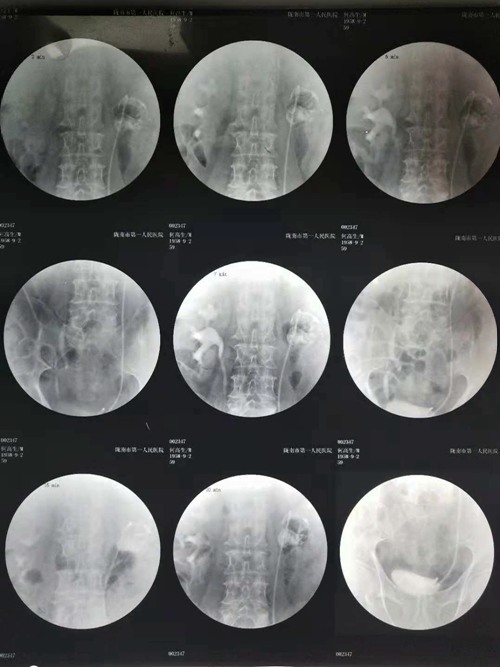

患者男性,67岁,主因左侧腰背部疼痛不适来我院就诊,入院后行泌尿系CT、静脉泌尿系造影、尿结核杆菌、尿抗酸染色、血沉等检查诊断为:左肾结核、左肾自截;随后行规范化抗结核治疗后,考虑到结核肾形态改变与周围组织粘连严重,决定为患者实施自截肾切除术。

(静脉肾盂造影)

经过缜密的术前准备,在李朝明主任的带领下,于9月28日成功为患者实施了腹腔镜下肾脏切除术。术后通过医护人员的精心照料,病人恢复良好,现已痊愈出院。